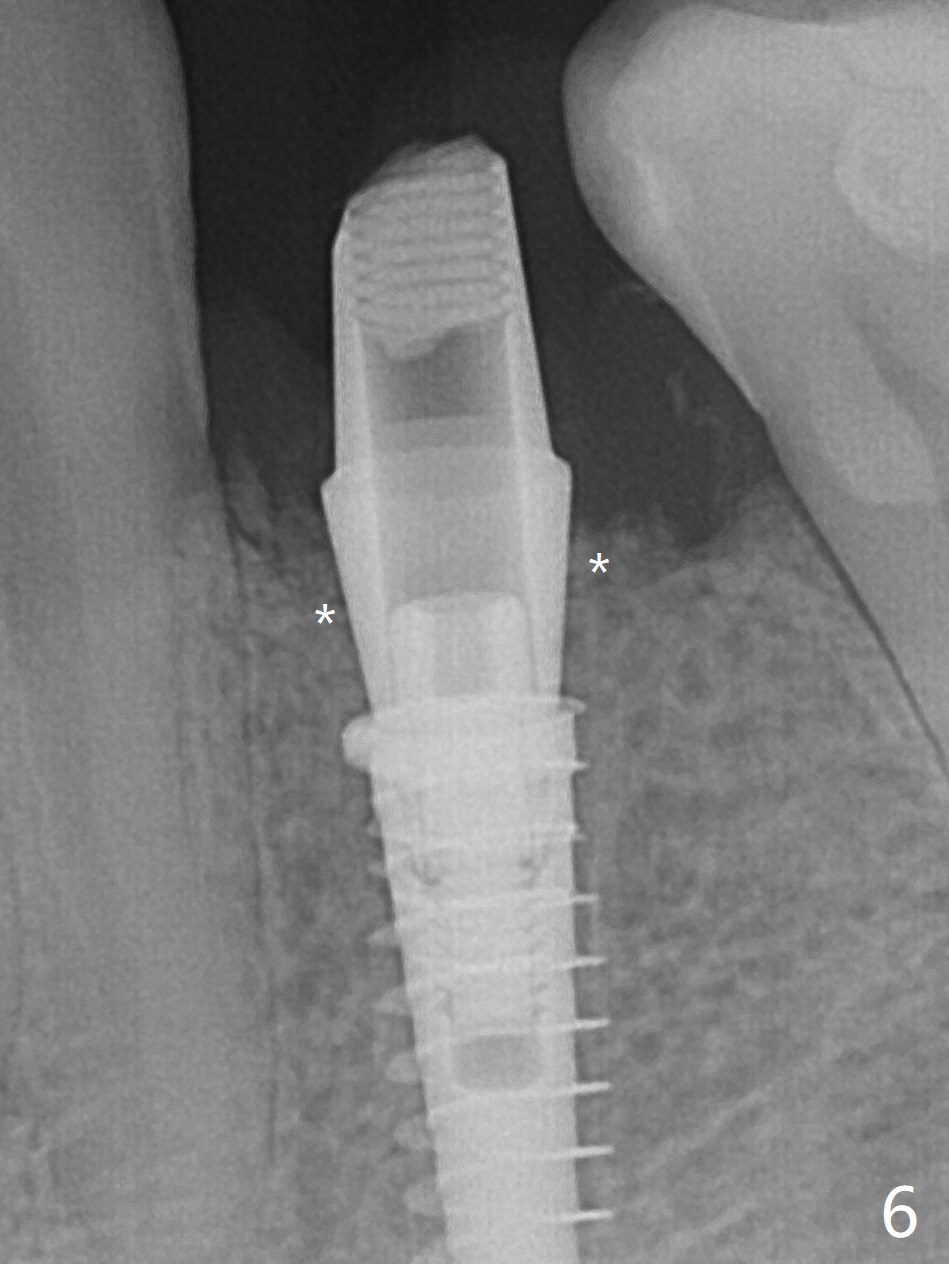

Three months post guide fabrication (coronavirus outbreak), the patient with loose post/crown returns for #21 extraction and immediate implant with guide (Fig.1 (*: post space)). In fact the root stump is flattened with diamond bur and 9 mm bone trimmer with guide before point drill. When the osteotomy finishes with 3.5x13 mm drill (under drilling with 10.5 mm offset), it has deviated buccal (Fig.2, 3,4); the outline of the bone trimmer mark is labeled by arrowheads in Fig.2. It appears that the center of the bone trimmer is dictated by that of the post space, as compared to Fig.1 *). When the root is removed except buccal shield (assuming that the deviation was due to the uneven surface of the root stump), the osteotomy is redone with guide, but remains buccal. Finally with buccal shield removal, a new lingual osteotomy is created free hand for a 4.5x11 mm implant (Fig.5) with 2-3 mm buccal gap for bone graft (Fig.6 * (literally)). In brief, bone trimmer also deviates according to resistance, basically irrelevant to the guide sleeve. The immediate provisional is intentionally removed 5 days postop to check whether a piece of gauze is retained in the socket as a gingival retraction cord for temporary crown fabrication; the buccal gap is kept with bone graft (Fig.7 *). No foreign body is in place. The margin of the abutment seems quite subgingival (Fig.8 *), but re-trimmed and polished provisional looks harmonious with the surrounding gingiva and the opposing dentition (Fig.9,10). The patient returns for prophy 2 months postop; the immediate provisional is removed for trimming and polishing. The bone graft seems to be integrated into a part of the gingiva (Fig.11 >). The abutment cuff appears to be too short.